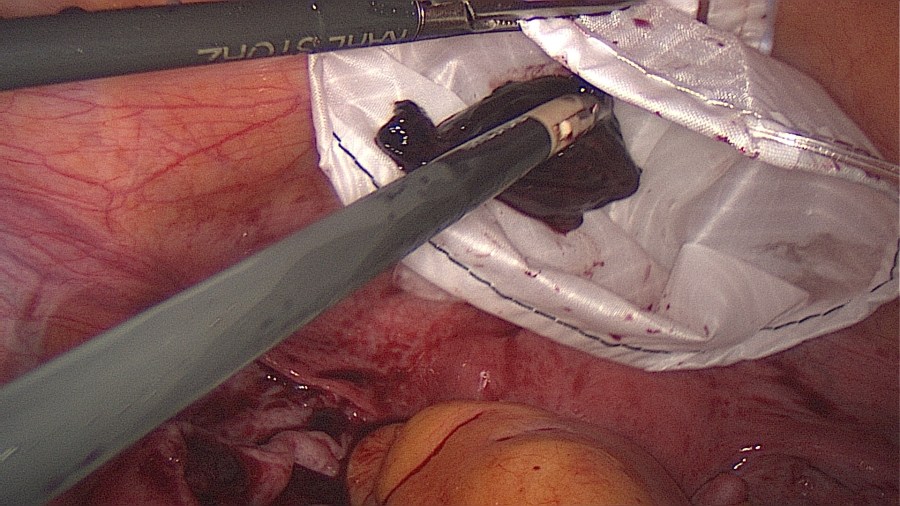

Grasp the contents with an atraumatic grasper and expell the tubal pregnancy en bloc. Failure to do so may increase risk of persistent ectopic tissue. Alternatively this may be performed with suction or aquadissection.

Bring the ectopic material inside a retriever bag and close it.